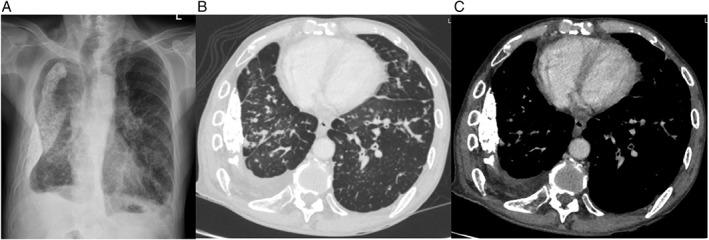

A 66-year-old Thai man with underlying asthma, history of traumatic right haemothorax, and sigmoid carcinoma with bladder invasion developed productive cough, whitish sputum, dyspnoea, and wheezing for 2 months. Physical examination showed generalized expiratory wheezing in both lungs. Computed tomography scan of the chest revealed diffuse thickening of bronchial wall, predominantly at lower lobes; several various sizes of pulmonary nodules; diffuse interlobular septal thickening; multiple enlarged mediastinal lymph nodes and hilar lymph nodes; and right pleural effusion. The patient was intubated for respiratory failure with persistent wheezing and, subsequently, with difficulty weaning from mechanical ventilation. Bronchoscopy was performed, which revealed diffuse multiple small mucosal nodules in both lungs. Pathology of the nodules showed foci of adenocarcinoma. Positive immunochemical staining with CDX2 confirmed the diagnosis of endobronchial metastasis of sigmoid carcinoma. This case highlighted a rare presentation of endobronchial metastasis from sigmoid carcinoma with persistent wheezing, respiratory failure, and difficulty in weaning from mechanical ventilation.

一名66岁的泰国男子,有哮喘病史、右侧创伤性血胸史,患有乙状结肠癌并侵犯膀胱,出现咳嗽、咳痰、呼吸困难和喘息2个月。体格检查显示双肺弥漫性呼气性哮鸣音。胸部计算机断层扫描显示支气管壁弥漫性增厚,主要位于下叶;有多个不同大小的肺结节;小叶间隔弥漫性增厚;纵隔和肺门多个淋巴结肿大;以及右侧胸腔积液。患者因呼吸衰竭伴持续性哮鸣音而插管,随后难以脱机。进行了支气管镜检查,发现双肺弥漫性多个小黏膜结节。结节病理显示腺癌灶。CDX2免疫化学染色阳性证实为乙状结肠癌支气管内转移。该病例突出了乙状结肠癌支气管内转移的罕见表现,伴有持续性哮鸣音、呼吸衰竭和脱机困难。